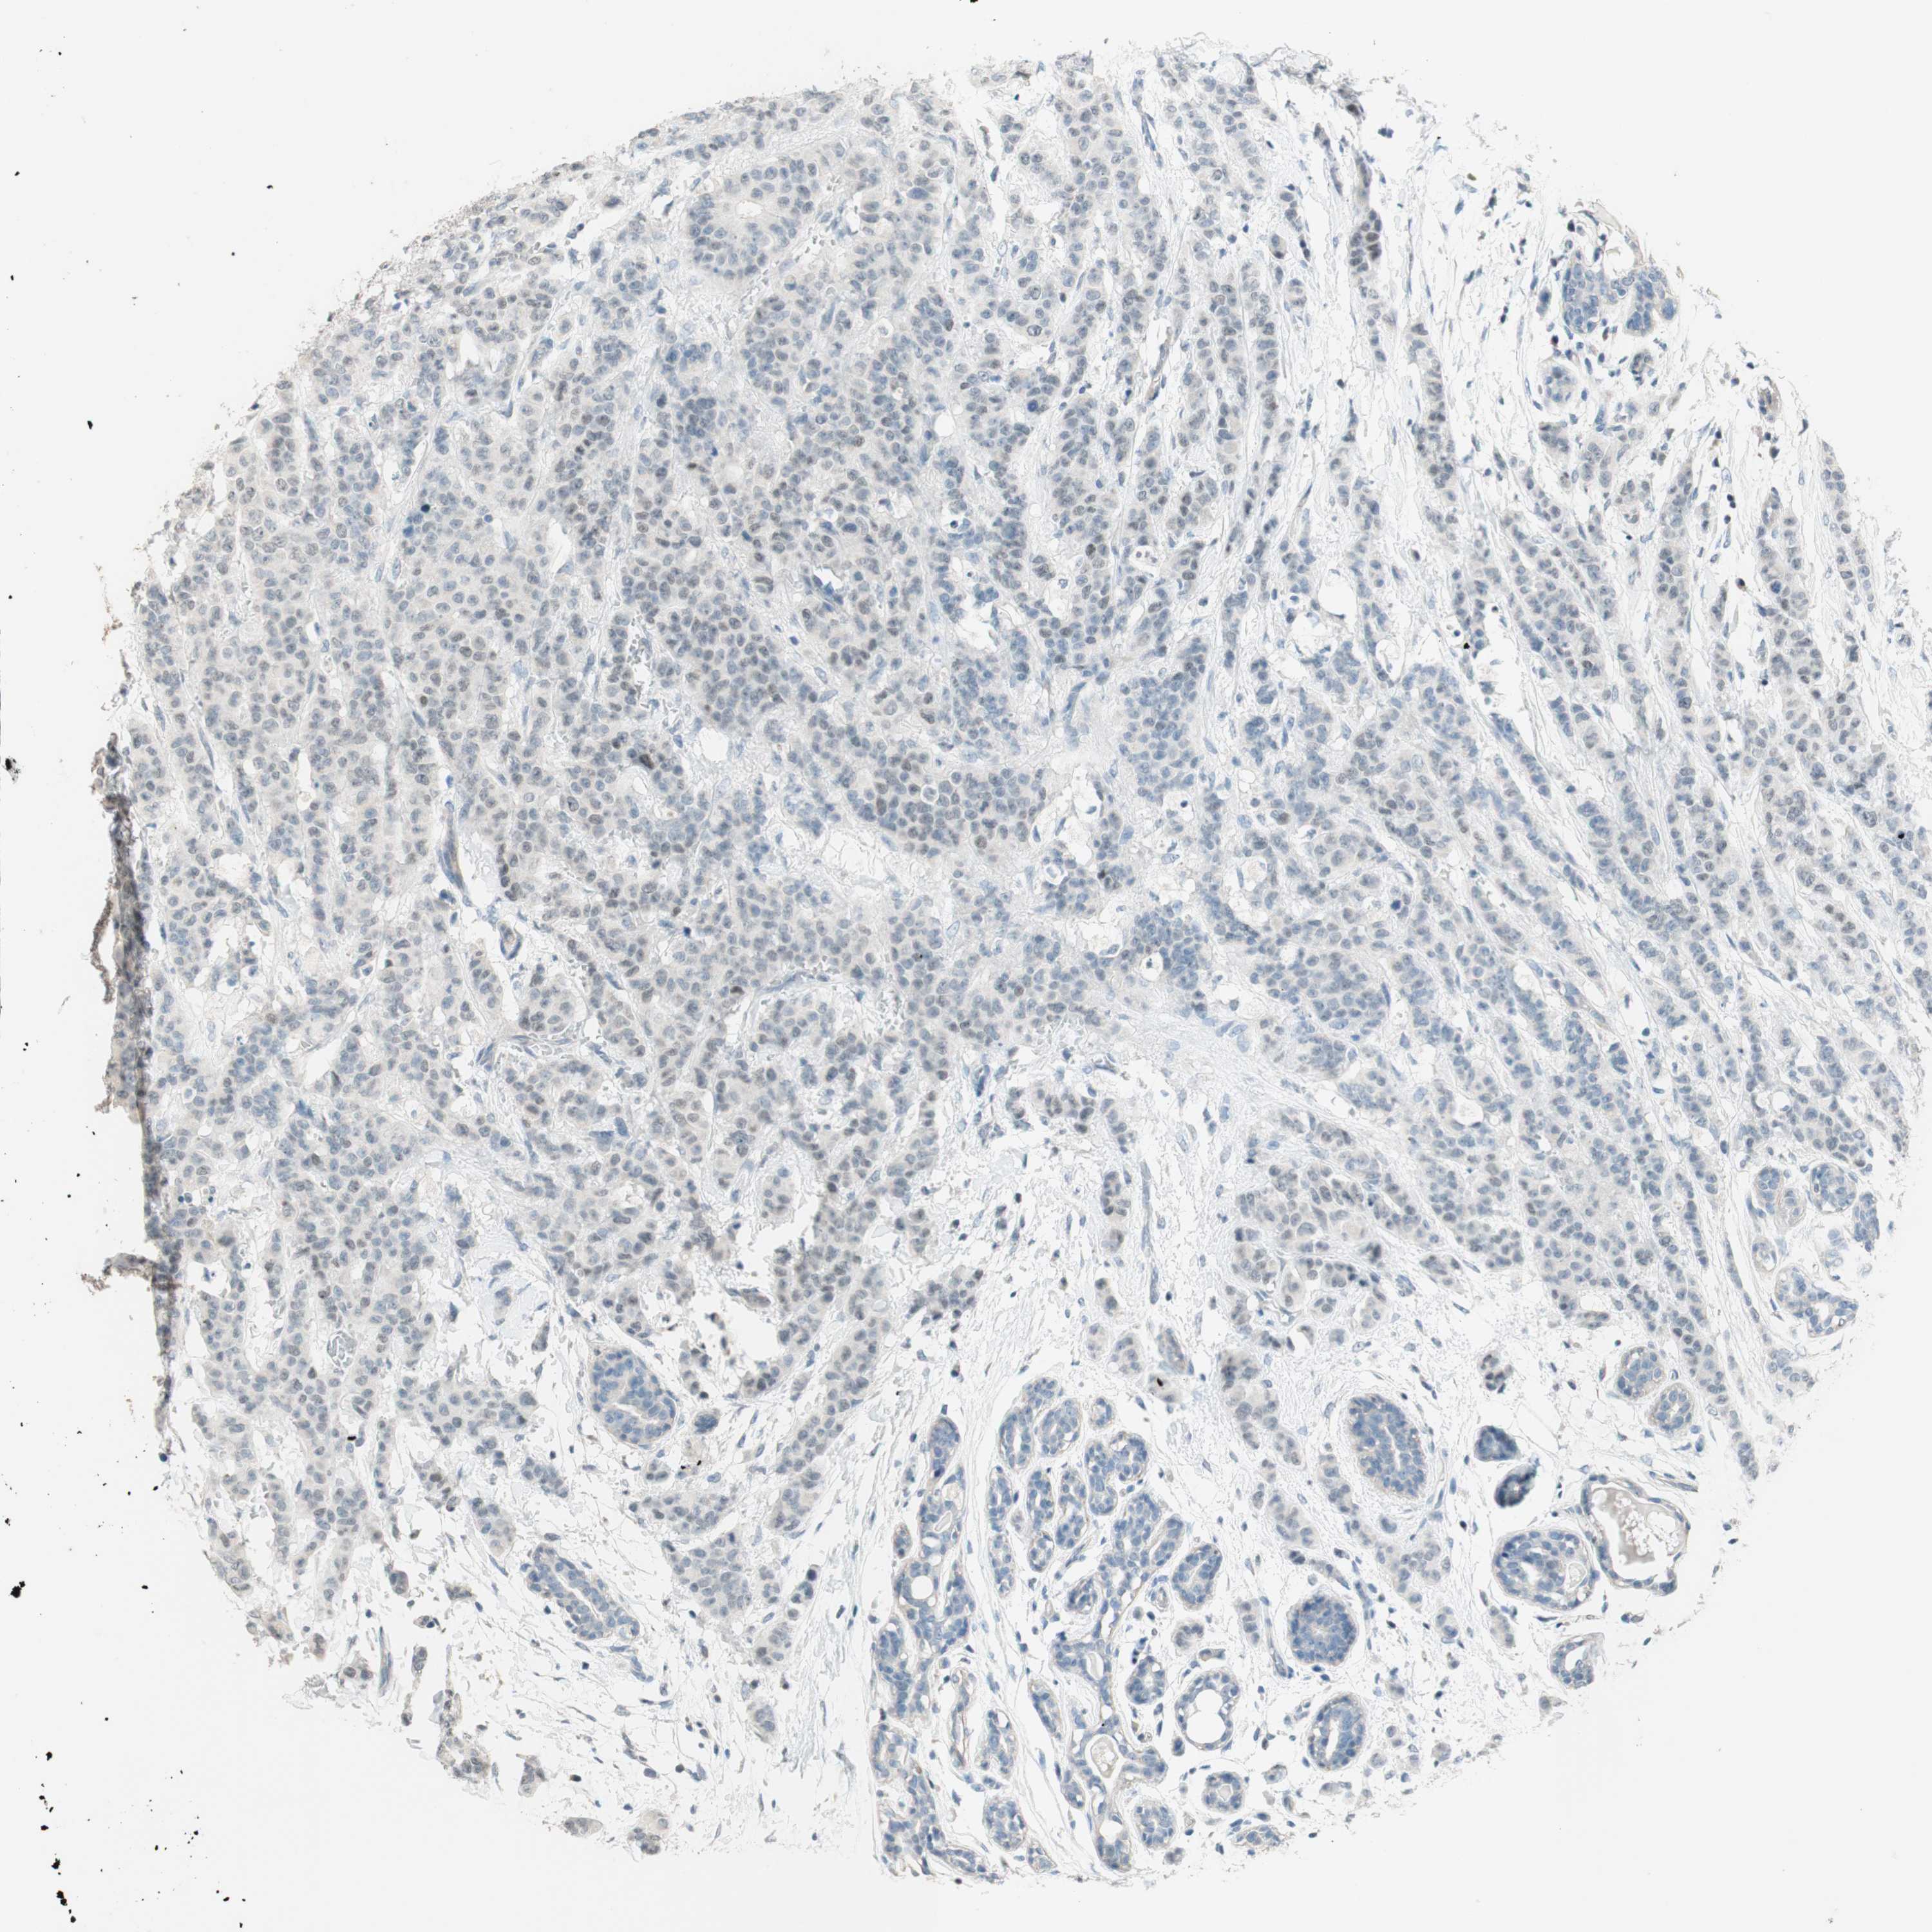

CANCER BREAST CANCER Show tissue menu

BRCA TCGA BRCA VALIDATION PROTEIN EXPRESSION